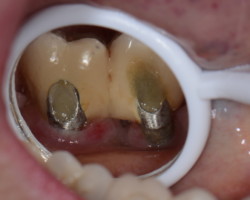

Avant-Après :